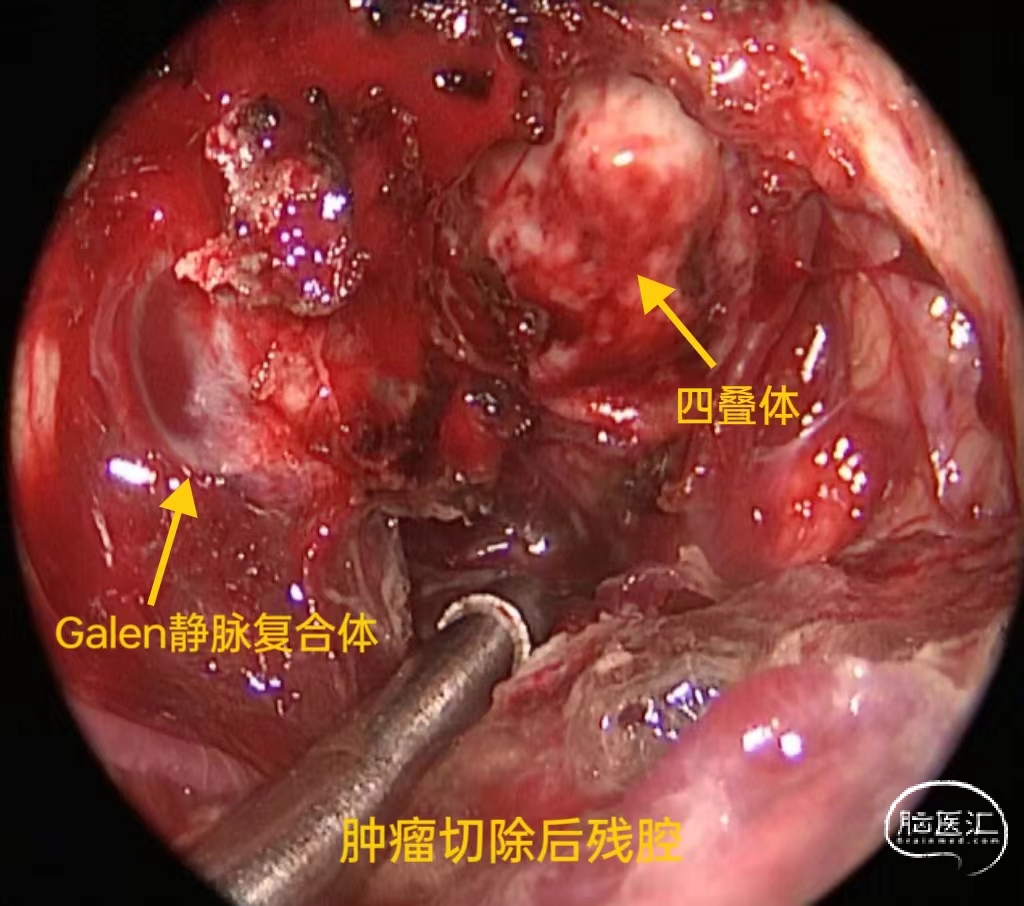

角度内镜,双吸引器下切除肿瘤

肿瘤切除后残腔

松果体区的肿瘤所在位置较深,周围环绕Galen静脉及其分支、四叠体等重要神经血管结构,手术切除难度及风险大,该例患者采用旁正中幕下小脑上入路,相比后正中入路大大减小了对小脑与天幕间桥静脉的损伤,神经内镜下幕下小脑上入路利用小脑与天幕间的自然间隙暴露深部的松果体区,这一手术入路不仅提供了适当的肿瘤暴露,而且保证了静脉结构的相对安全。而神经内镜的辅助更提供了高清的视野,有利于肿瘤的充分暴露,在神经血管解剖保留的前提下提高肿瘤全切率。